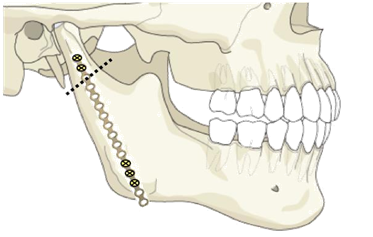

The condylar neck fracture was identified through the preauricular incision and the proximal segment was verified to be displaced medially. A submandibular incision was used to expose the angle of the right hemimandible. A subperiosteal tunnel from the superior incision to the inferior incision was created using a Freer. By sliding the Freer subperiosteally, the Facial nerve was safely avoided (Figure 3) (Figure 4). After the condylar head was identified and returned to the empty glenoid fossa the fragment was rotated then held and oriented by means of a 7 mm. titanium self-tapping screw that was screwed half-way into the condylar segment that served as its handle and stabilizer. The angle of the right hemimandible was then grasped using a bone holder and downward traction was applied to make space to facilitate repositioning the condylar fragment. MMF and Gilmer wires have not been applied. This was to facilitate traction of the mandible downwards.

A 16-hole 1.5 mm semi-rigid, miniplate was slid through the tunnel and fixed to the condylar fragment with two screws. The caudal portion of the titanium plate was then used to fine tune the distance and orientation of the condylar fragment. The lie was verified visually and by palpation using the end of the Freer by feeling for the bones. Three screws were then fixed on the bottom of the plate near the angle of the mandible. The excess miniplate was molded to the edge of the angle of the mandible (Figure 5).

Figure 3 Placement of long screw and Proximal End of the Titanium Plate on the Proximal Segment of the Condylar Neck Fracture (dotted lines show the lie of the miniplate).

Figure 4 Distal End of the Titanium Plate fixed to the Ramus of the Mandible (dotted lines show the lie of the miniplate).

Figure 5 A Diagrammatic Representation of the Condylar Neck Fracture (dotted lines) with the length of the Miniplate Applied and the placement of the screws.